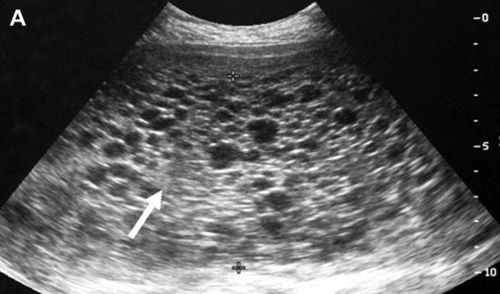

Khi siêu âm thấy lốm đốm được ví như hình ảnh tuyết rơi, hình ảnh chùm nho

Làm xét nghiệm thấy nồng độ ßhCG tăng rất cao, cao hơn tuổi thai và tăng nhanh liên tục. Khi siêu âm cũng không nghe thấy tim thai, không thấy hình ảnh phôi thai mà chỉ thấy lốm đốm được ví như hình ảnh tuyết rơi, hình ảnh chùm nho.